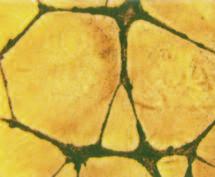

„Brillano di rosso le stelle?” immagine al microscopio di cellule tumorali, che per effetto dei micronutrienti si avviano a morire in modo naturale.

Immagine eseguita presso l’istituto di ricerca del Dr Rath a Santa Clara, in California

L’intera galleria di foto è disponibile nel sito: www.dr-rath-humanities-foundation.org/exhibition/index.html.